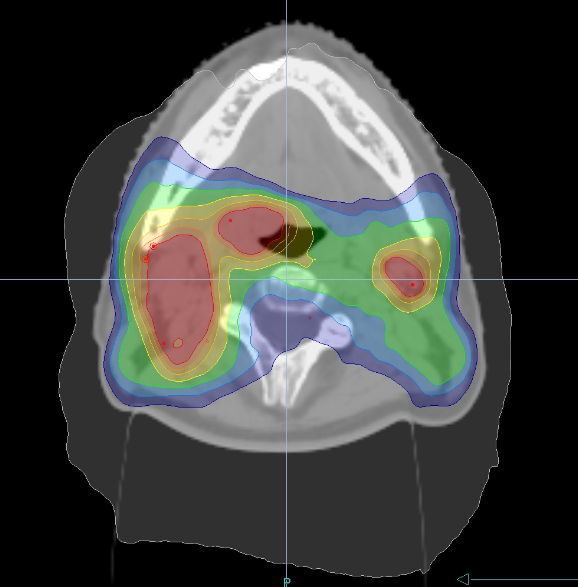

咽頭がんや喉頭がんなど主に頸部に発生するがんです。手術が困難なことや、術後の後遺症が大きいことなどから放射線治療の適応となることが多い疾患です。頭頸部には視神経・視交叉、脳幹、脊髄、耳下腺、下顎骨などの重要な臓器が密集しており、従来の治療では重篤な副作用が出現したり治療効果が落ちたりといったことが生じやすい領域でした。IMRTにより、重要臓器を極力さけながら病変部に十分な放射線量を投与することが可能となりました。副作用は頸部の広範囲の皮膚炎や粘膜炎による疼痛、唾液腺障害による唾液分泌低下、味覚障害、顎骨壊死など多岐にわたります。(図:頭頸部がんに対するIMRT)・乳がん